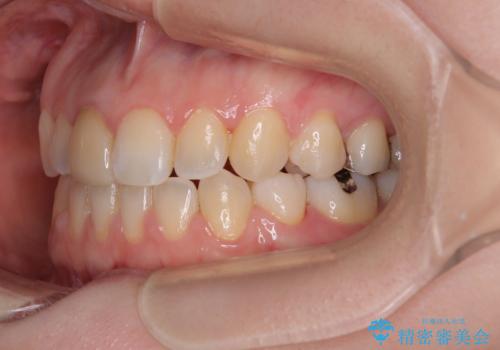

【モニター】後戻りでできた隙間 ワイヤー装置での再矯正

- 学生時代に行った抜歯矯正の後戻りで、隙間ができてしまったことを気にして来院された患者様です。

マウスピース矯正を検討されていましたが、後戻りの隙間が非常に大きく、奥歯を前方に移動させる必要があるため、ワイヤー装置にて矯正治療を行うこととしました。

舌の突出癖が非常に強く、その影響で隙間ができてしまったので、舌のトレーニングをしっかりと行っていただきました。